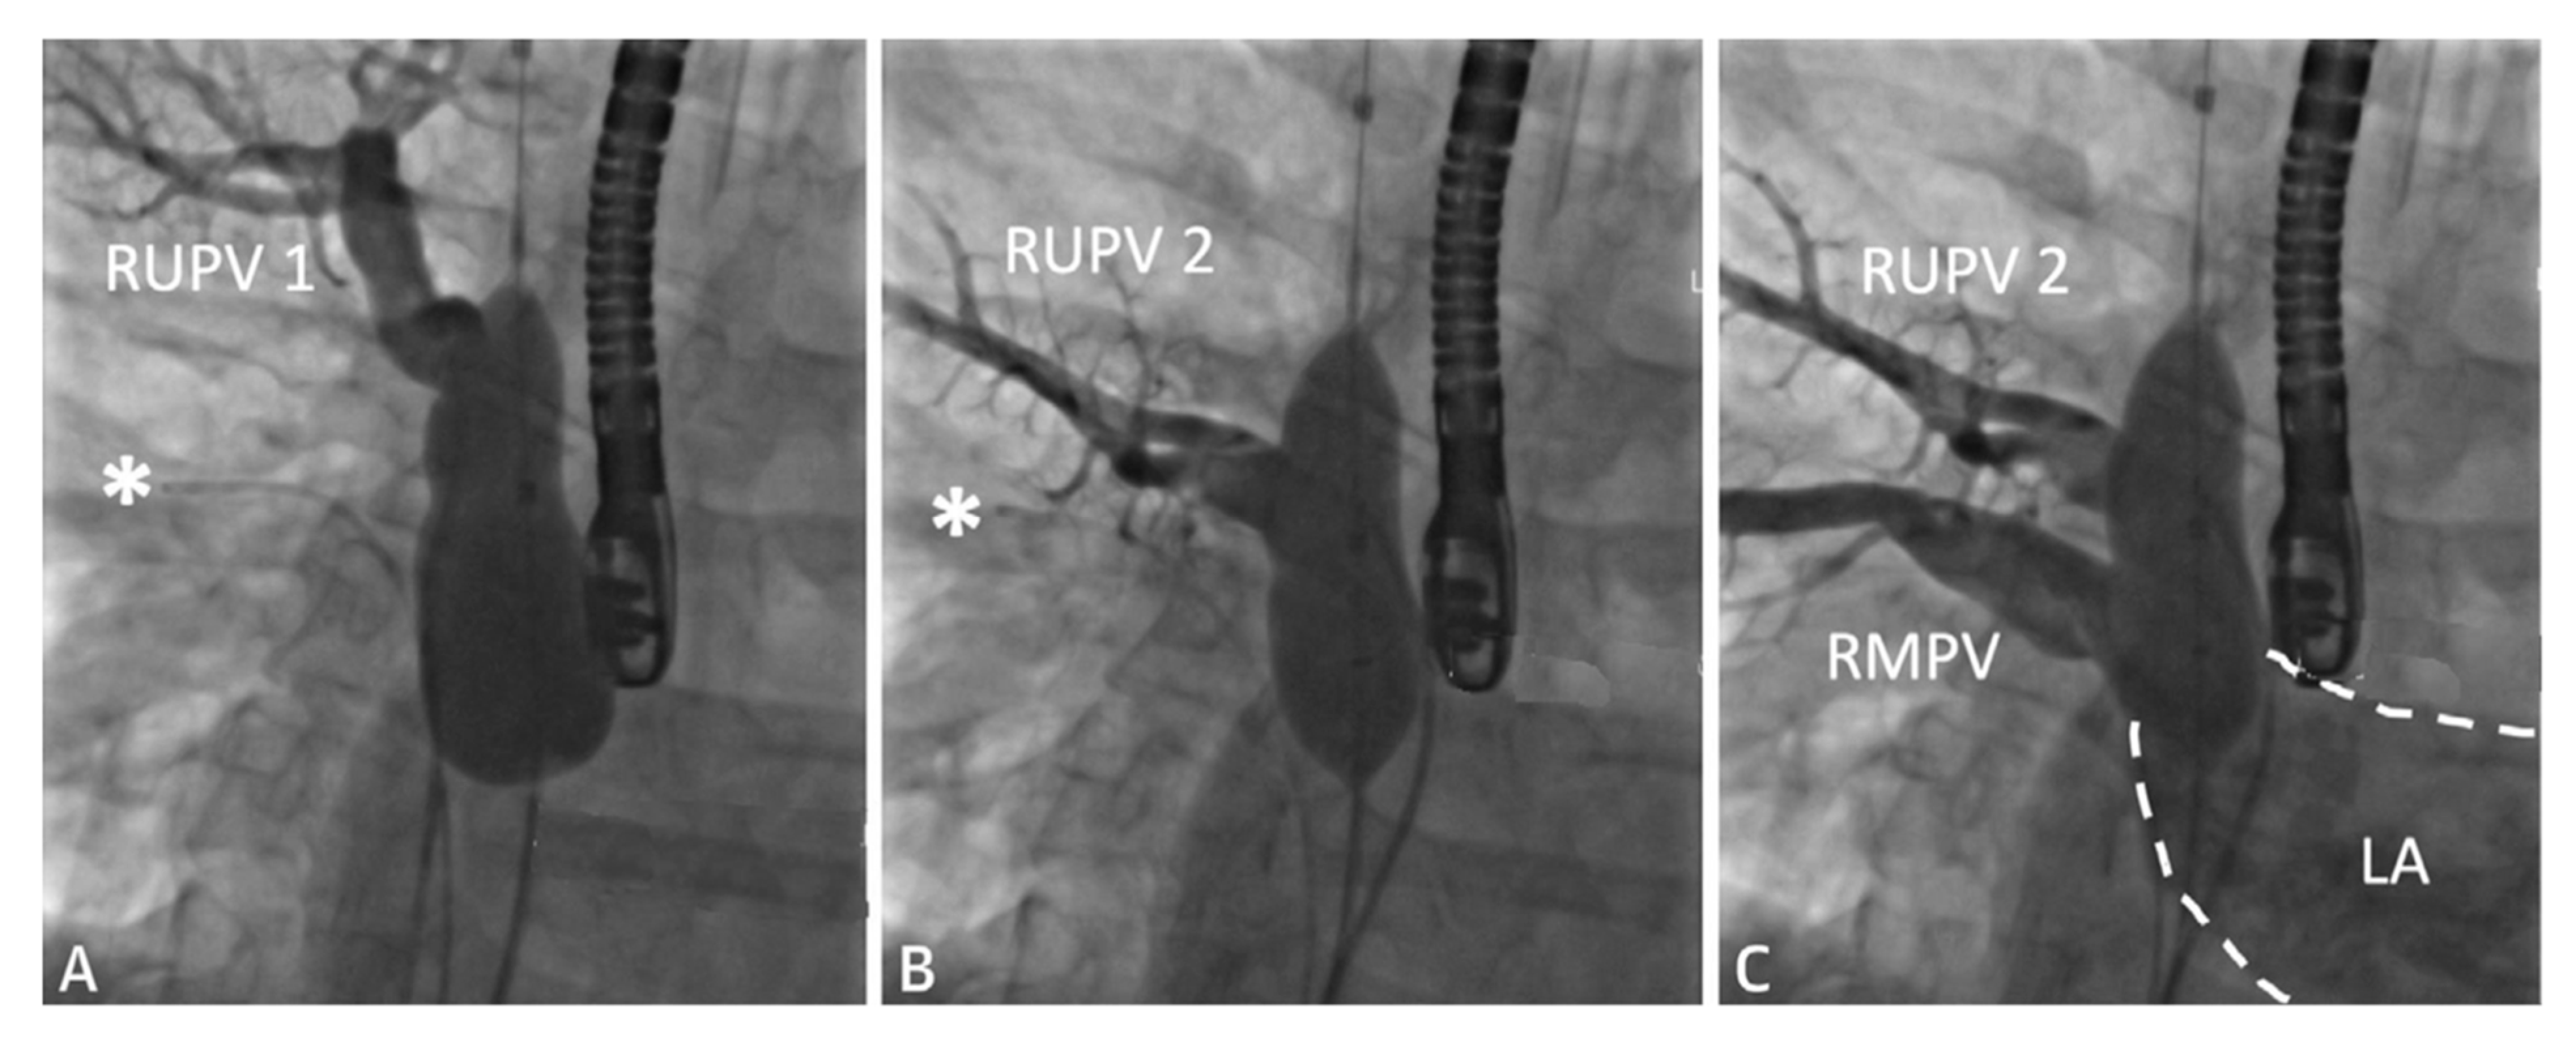

2.1. Sinus Venosus Atrial Septal Defect (SVASD)

| Sinus venosus atrial septal defect | SVASD |

| Right upper pulmonary vein | RUPV |

| Left atrium | LA |

| Right atrium | RA |

| Right middle pulmonary vein | RMPV |

| Anomalous pulmonary vein | aPV |